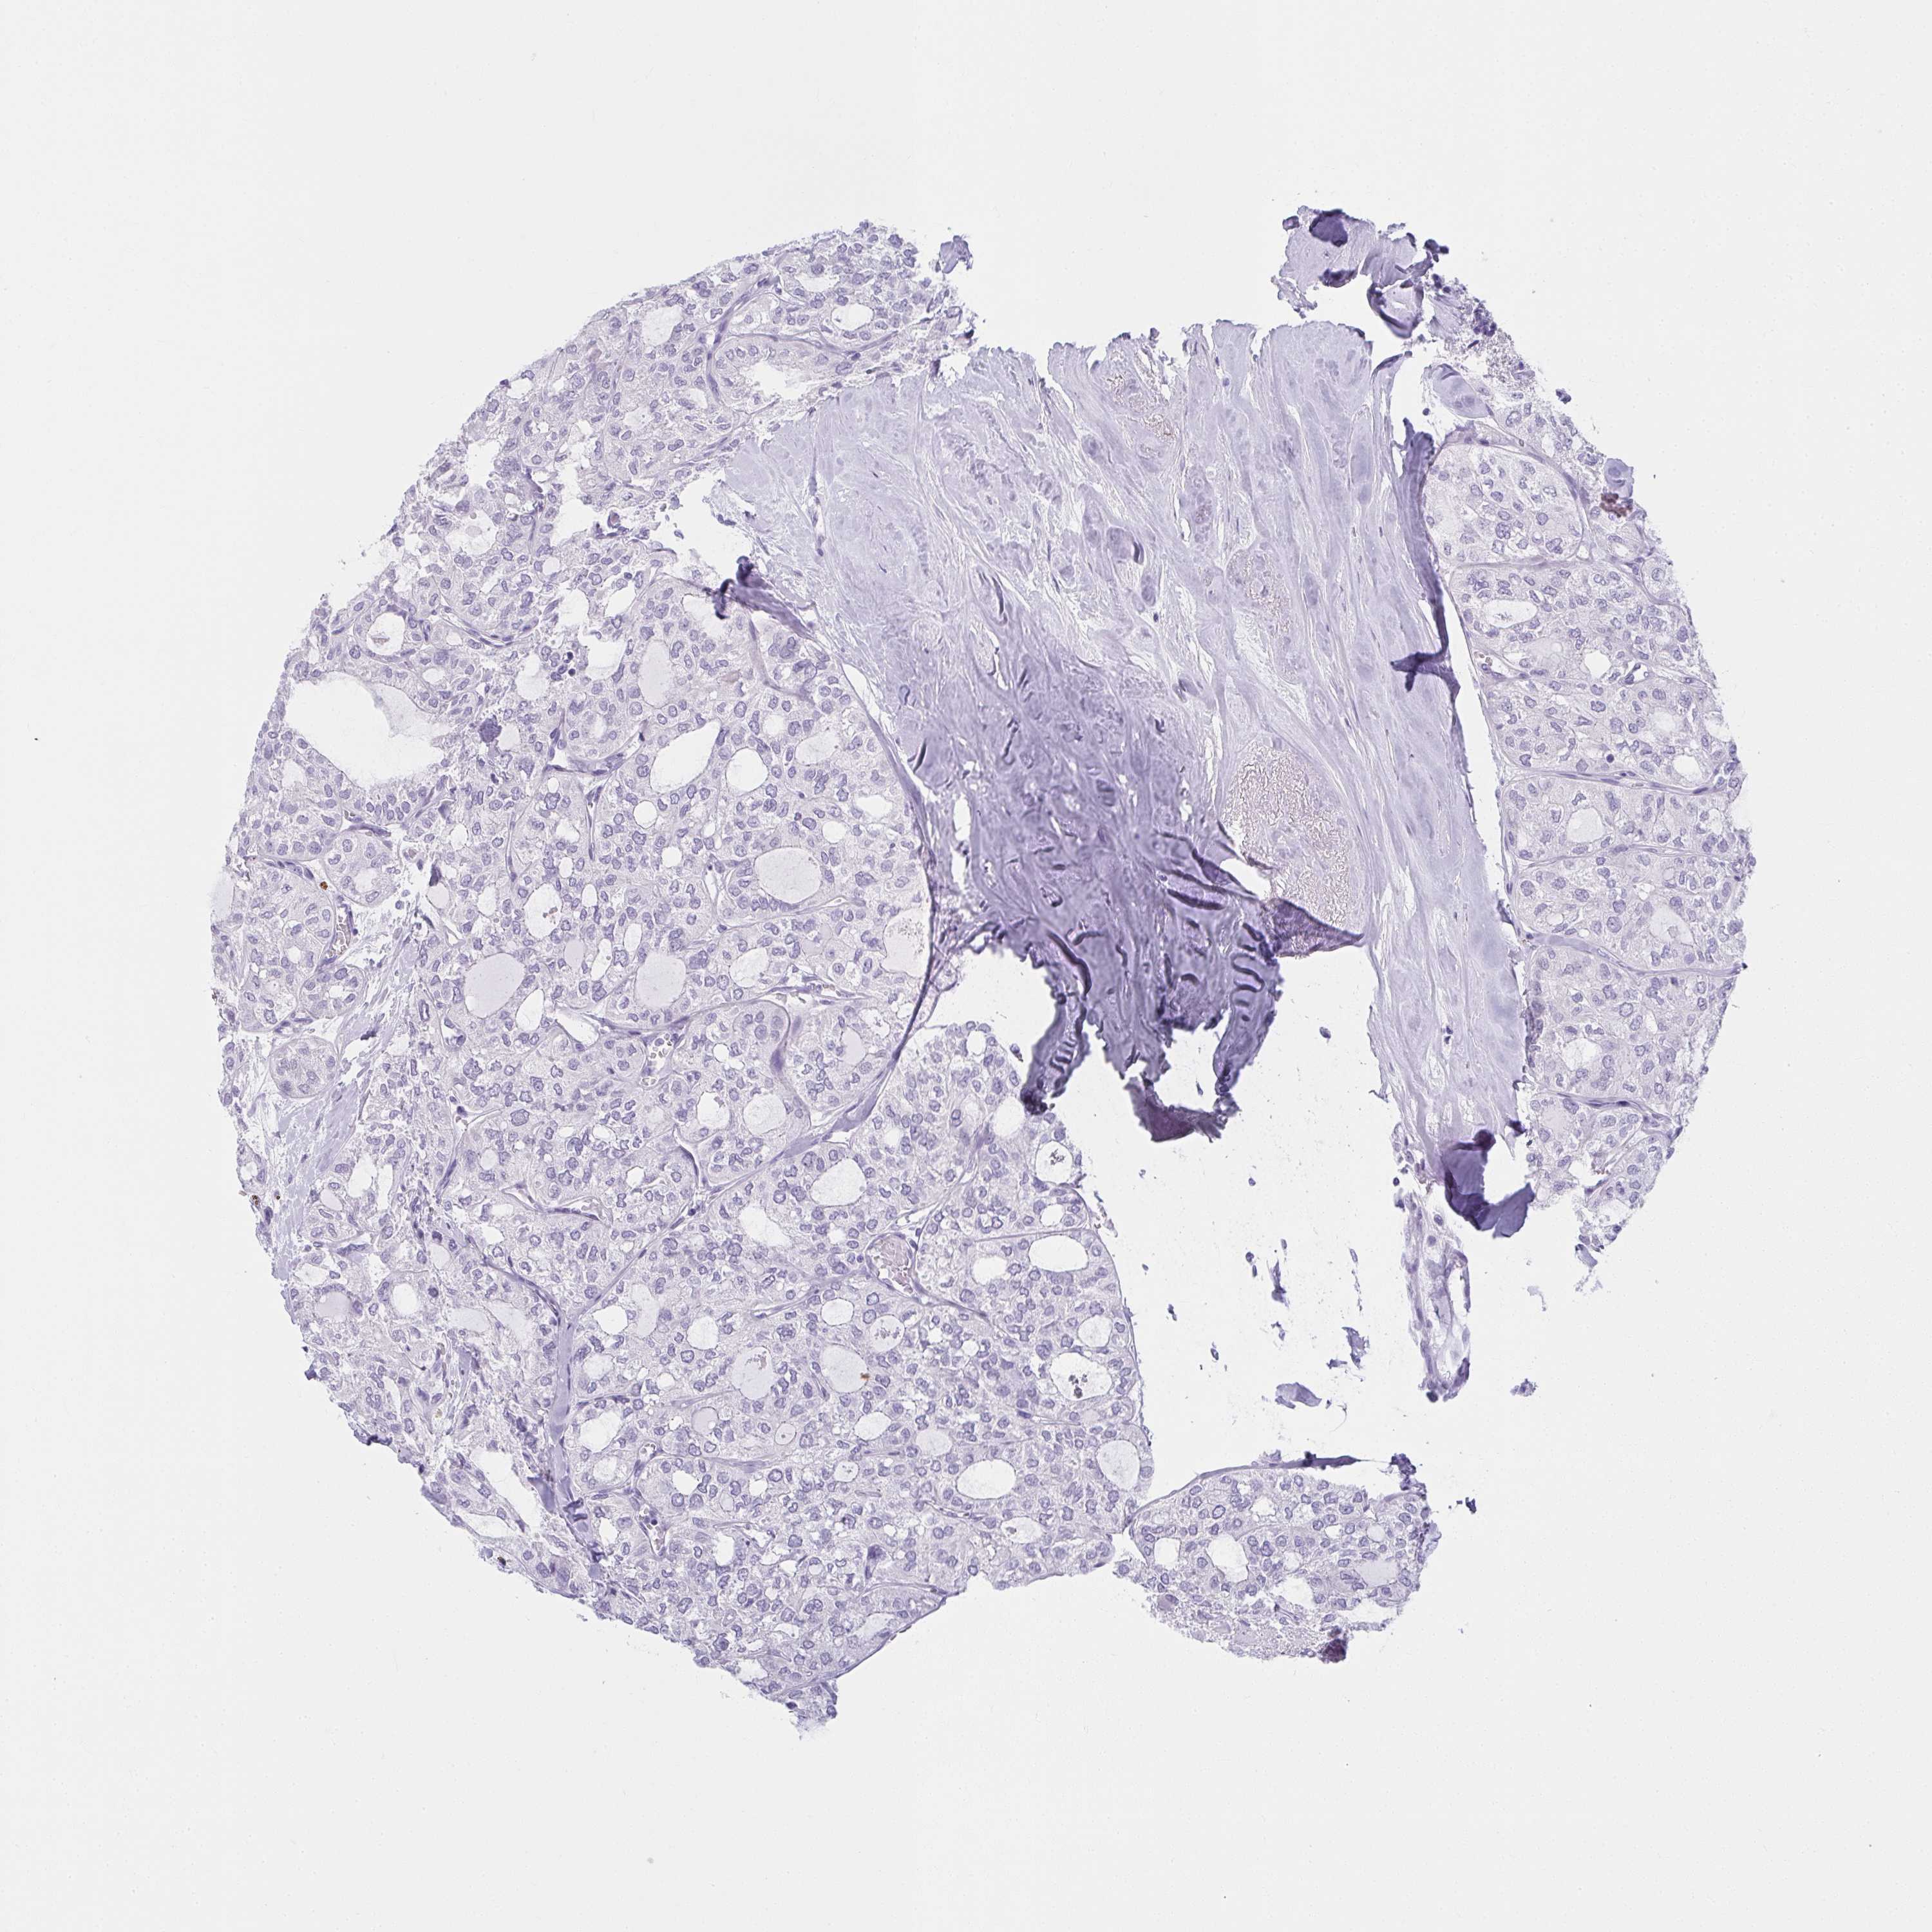

THYROID CANCER - Protein expressioni

A mouse-over function shows sample information and annotation data. Click on an image to view it in a full screen mode. Samples can be filtered based on level of antibody staining by selecting one or several of the following categories: high, medium, low and not detected. The assay and annotation is described here.

Note that samples used for immunohistochemistry by the Human Protein Atlas do not correspond to samples in the TCGA dataset.

Antibody stainingi

Antibody staining in the annotated cell types in the current human tissue is reported as not detected, low, medium, or high, based on conventional immunohistochemistry profiling in selected tissues. This score is based on the combination of the staining intensity and fraction of stained cells.

Each image is clickable and will lead to virtual microscopy that enables deeper exploration of all samples and also displays staining intensity scores, fraction scores and subcellular localization as well as patient and tissue information for each sample.

Antibody HPA035152

Staining

High

Medium

Low

Not detected

Intensity

Strong

Moderate

Weak

Negative

Quantity

>75%

75%-25%

<25%

None

Location

Nuclear

Cytoplasmic/membranous

Cytoplasmic/membranous,nuclear

Papillary adenocarcinoma, NOS

Follicular adenoma carcinoma, NOS